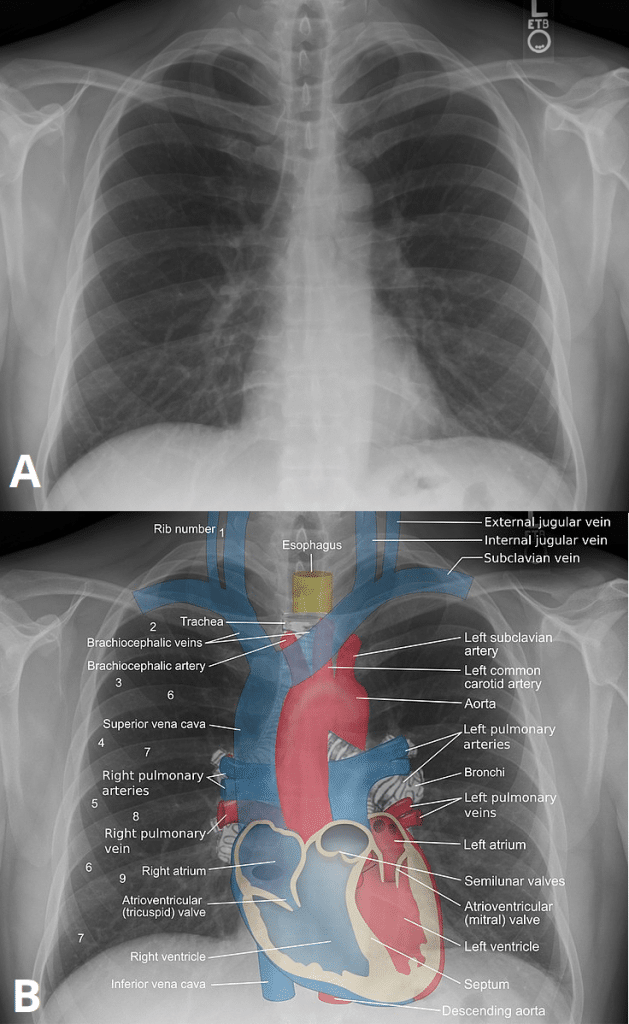

Plain film x-ray is the most common diagnostic radiological modality used in hospitals today. They were first discovered and used for imaging purposes by Wilhelm Röntgen on 8th November 1895, when he took an image of his wife’s hand. In this article, we shall look at the basic science underpinning x-rays, and the principles of their interpretation. Pro Feature - 3D Model You've Discovered a Pro Feature Access our 3D Model Library Explore, cut, dissect, annotate and manipulate our 3D models to visualise anatomy in a dynamic, interactive way. Learn More Basic Principles X-rays are a type of electromagnetic radiation (just like visible light). There are three criteria that must be met to allow electromagnetic radiation to be used for imaging purposes: Ability to create to the electromagnetic radiation at the wavelength required Ability to focus the radiation on a particular area Ability to detect the radiation once it has passed through the patient. The radiation is created when an electric current is generated from a high voltage generator. This causes electrons to “boil-off” from the cathode end of an X-ray tube assembly. These electrons are emitted from a filament on the cathode and rush towards a target material known as the anode. This process is known as thermionic emission. The electrons emitted by the cathode rush towards the anode, which holds a disc made of tungsten. When the electrons collide with the tungsten, several interactions occur at the atomic level. One of these interactions causes electrons to be expelled from the outer orbits of the atoms releasing a X-ray photon. Energy levels of the X-ray photon will vary and can be adjusted when selecting a parameter known as kVP or kilovolts peak. These X-rays then travel through a focusing cup, focusing and accelerating the photons towards the area of the body to be imaged. Traditionally, radiographic film was used known as double emulsion film containing silver nitrate. With technological advancements, many instutions will be using a cassette receptor or if newer technology is available, a digital plate receptor may be used instead. These receptors are placed behind the patient to capture the x-ray photons that are transmitted through the patient and ultimately form the image. <a href="https://pulseradeducation.com"> Pulse Radiology Education</a> Fig 1How an x-ray is generated. Interpreting an X-Ray The interpretation of an x-ray film requires sound anatomical knowledge, and an understanding that different tissue types absorb x-rays to varying degrees: High density tissue (e.g. bone) – absorb x-rays to a greater degree, and appear white on the film. Low density tissue (e.g the lungs) – absorb x-rays to a lesser degree, and appear black on the film. Intermediate density tissue (e.g. muscle and fat) – appears as shades of grey on the x-ray film. It is important to appreciate that x-rays only give a 2D superimposed view of the body part that has been imaged. Therefore, it may be necessary to take multiple views of the same area from different angle (e.g. in cases of suspected fracture), to gain a full understanding of the injury. By Mikael Häggström. Based on source images by ZooFari, Stillwaterising and Gray's Anatomy [CC BY-SA 3.0], via Wikimedia Commons Fig 2Illustration of the mediastinal structures in a normal chest radiograph. Comparison to Other Imaging Techniques The biggest advantage with plain film X-rays is the amount of radiation involved. It offers lower dosage compared to CT, and certain studies are performed relatively quickly (Chest X-rays). They are often used as an initial screening to rule out anything obvious before an advanced modality is used such as CT or MR. However, plain film X-rays procedures are being replaced by CT and MR due to advancements in technology. There are CT scanners available on the market now that offer radiation dosage levels as low as plain film X-rays. Below is a summary table of the common imaging modalities. Depending on the tissue being imaged, the urgency of the investigation and the level of detail required, any of these techniques may be preferred: Factor CT (CT abdo used as example) MRI X-ray (CXR used as example) Ultrasound Duration 3-7 minutes 30-45 min 2-3 min 5-10 minutes Cost Cheaper Expensive Cheap Cheap Dimensions 3 3 2 2 Soft tissue Poor detail Excellent detail Poor detail Poor detail Bone Excellent detail Poor detail Excellent detail Poor detail Radiation 10mSv None 0.15mSv None Do you think you’re ready? Take the quiz below Pro Feature - Quiz Plain Film X-Ray Question 1 of 3 Submitting... Skip Next Rate question: You scored 0% Skipped: 0/3 1800 More Questions Available Upgrade to TeachMeAnatomy Pro Challenge yourself with over 1800 multiple-choice questions to reinforce learning Learn More Rate This Article